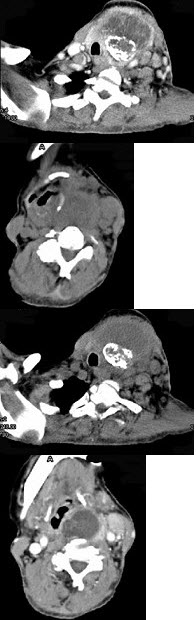

女,64岁,双甲状腺占位40余天。如图所示甲状腺病灶应诊断为( )

A:结节性甲状腺肿

B:甲状腺腺瘤

C:甲状腺癌并淋巴结转移

D:甲状腺转移瘤

E:甲状腺结核